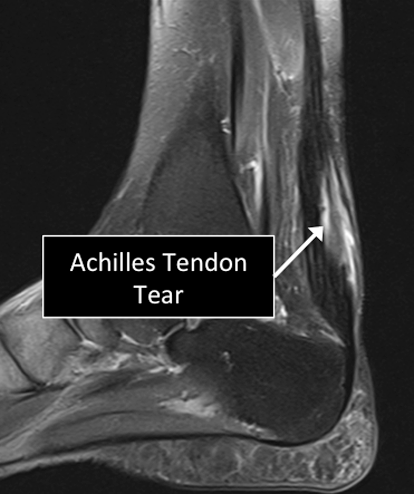

Several injuries or diseases affecting the tendon can be diagnosed using MRI.

Common things affecting the tendons include degenerative or traumatic tears, abnormal calcium deposition in the tendons or adjacent to them, tendon degeneration, ganglion cysts (abnormal collections of fluid) in or adjacent to tendons, among others.

Ankle MRI examinations showing normal (top) and abnormal (bottom) Achilles tendon.

Why Translational MRI of the ankle?

- In the ankle, as in many other parts of the body there are certain structures that can’t be seen (they look black or dark) with the standard MRI.

- There are new “software” programs that allow us to see structures with different contrast (bright versus dark).

- Some of these “invisible” or dark structures are unique to the ankle (e.g. the Achilles tendon) and others are found in other parts of the body (e.g. cartilage, ligaments, other tendons, cortical bone).